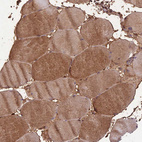

Immunohistochemical staining of human colon shows strong cytoplasmic positivity in glandular cells.